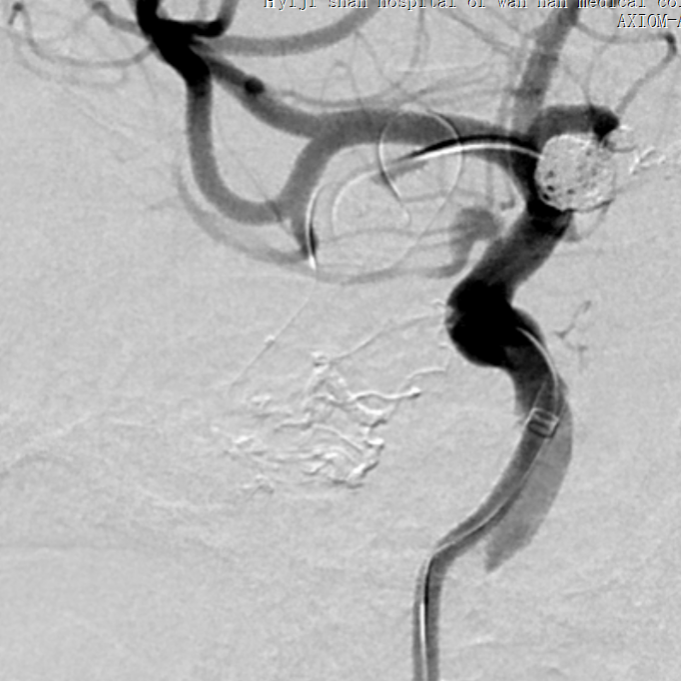

入院后脑血管造影检查提示:右侧颞叶动静脉畸形,由右侧大脑中动脉两分支血管参与供血,右侧大脑后动脉一分支血管参与供血,畸形团大小约1.1*1.3cm,通过侧裂静脉经皮层静脉引流入上矢状窦前部;并可见右侧大脑后动脉供血畸形团的分支血管血流相关性动脉瘤两枚。

1. 通过椎动脉先将Echelon 10微导管在导丝导引下超选至远端动脉瘤,填塞弹簧圈(Cosmos 4mm/12cm,Jasper 3.5mm/10cm,Axium 3mm/8cm,Jasper 2.5mm/8cm),然后逐渐回撤微导管至近端动脉瘤填塞(Axium Prime 4mm/12cm),最后可见向畸形团供血明显减弱,远端动脉瘤不显影,近端动脉瘤仍有显影。

2. 栓塞大脑中动脉供血的分支血管及畸形团

将Echelon 10微导管超选至右侧大脑中动脉分叉部分支血管远端,微导管造影确认系畸形团供血动脉,DMSO冲管后注射Onyx胶再行造影,可见该分支血管远端闭塞,予以撤出Echelon 10微导管。

用Apollo微导管超选大脑中动脉M1段分支血管直至畸形团内,进行微导管造影确认微导管进入畸形团,DMSO冲管,缓慢注射Onyx 18,路图下可见胶在畸形团内弥散,最后颈内动脉造影可见畸形团完全不显影,但是胶反流导致拔管困难,透视下可见血管移位变形明显。